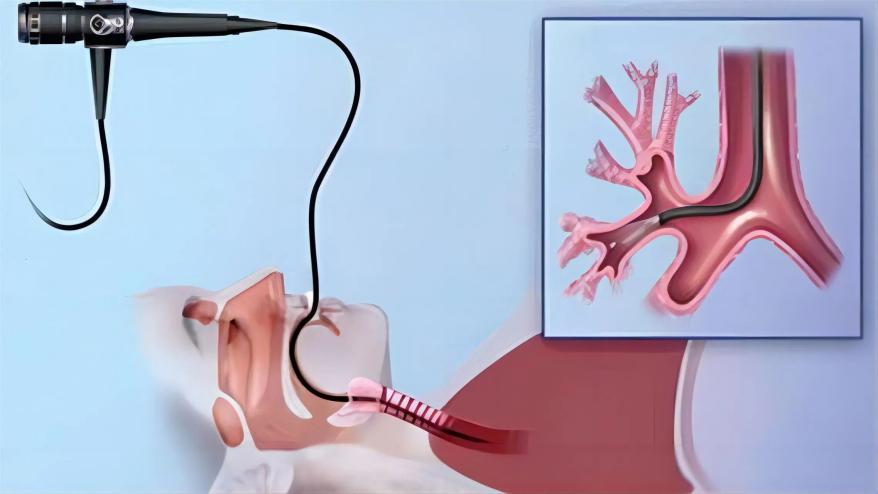

在医学检查中,支气管镜如同一根搭载高清“鹰眼”的细长探针,能够深入人体气管、支气管甚至肺部,直视气道内部的真实情况,精准捕捉那些常规检查难以发现的病灶。支气管镜不仅是一项重要的诊断工具,更是呼吸系统疾病诊疗的“利器”。

支气管镜是一种用于检查气管和支气管的内窥镜设备,通过支气管镜检查,呼吸科医生能够检查呼吸道的内部结构,识别病变或异常情况,进行相关的诊断,如灌洗、刷检、活检、不明原因咯血的诊断以及肺移植前的评估等。

支气管镜分为硬质支气管镜和可弯曲支气管镜,两种支气管镜各自具有相应的优点,临床上可弯曲支气管镜更为常用。目前,支气管镜检查已成为支气管、肺和胸腔疾病诊断、治疗及抢救不可或缺的重要手段。